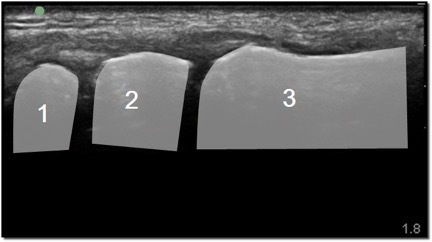

Hand CMC Joint Image

Scaphoid

Trapezium

Base of the 1st Metacarpal